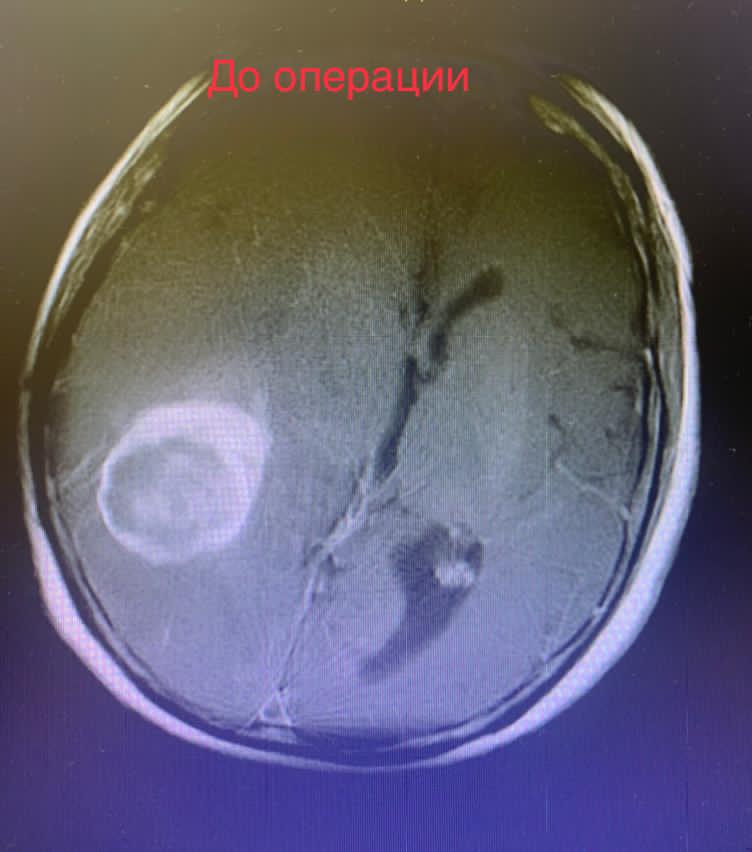

Проведены дополнительные обследования. МРТ головного мозга выявила опухоль головного мозга размером 3х4х4 см, с большим перифокальным отеком и смещением срединных структур головного мозга, что требовало неотложного нейрохирургического вмешательства.

Выполнено микрохирургическое удаление опухоли единым блоком.